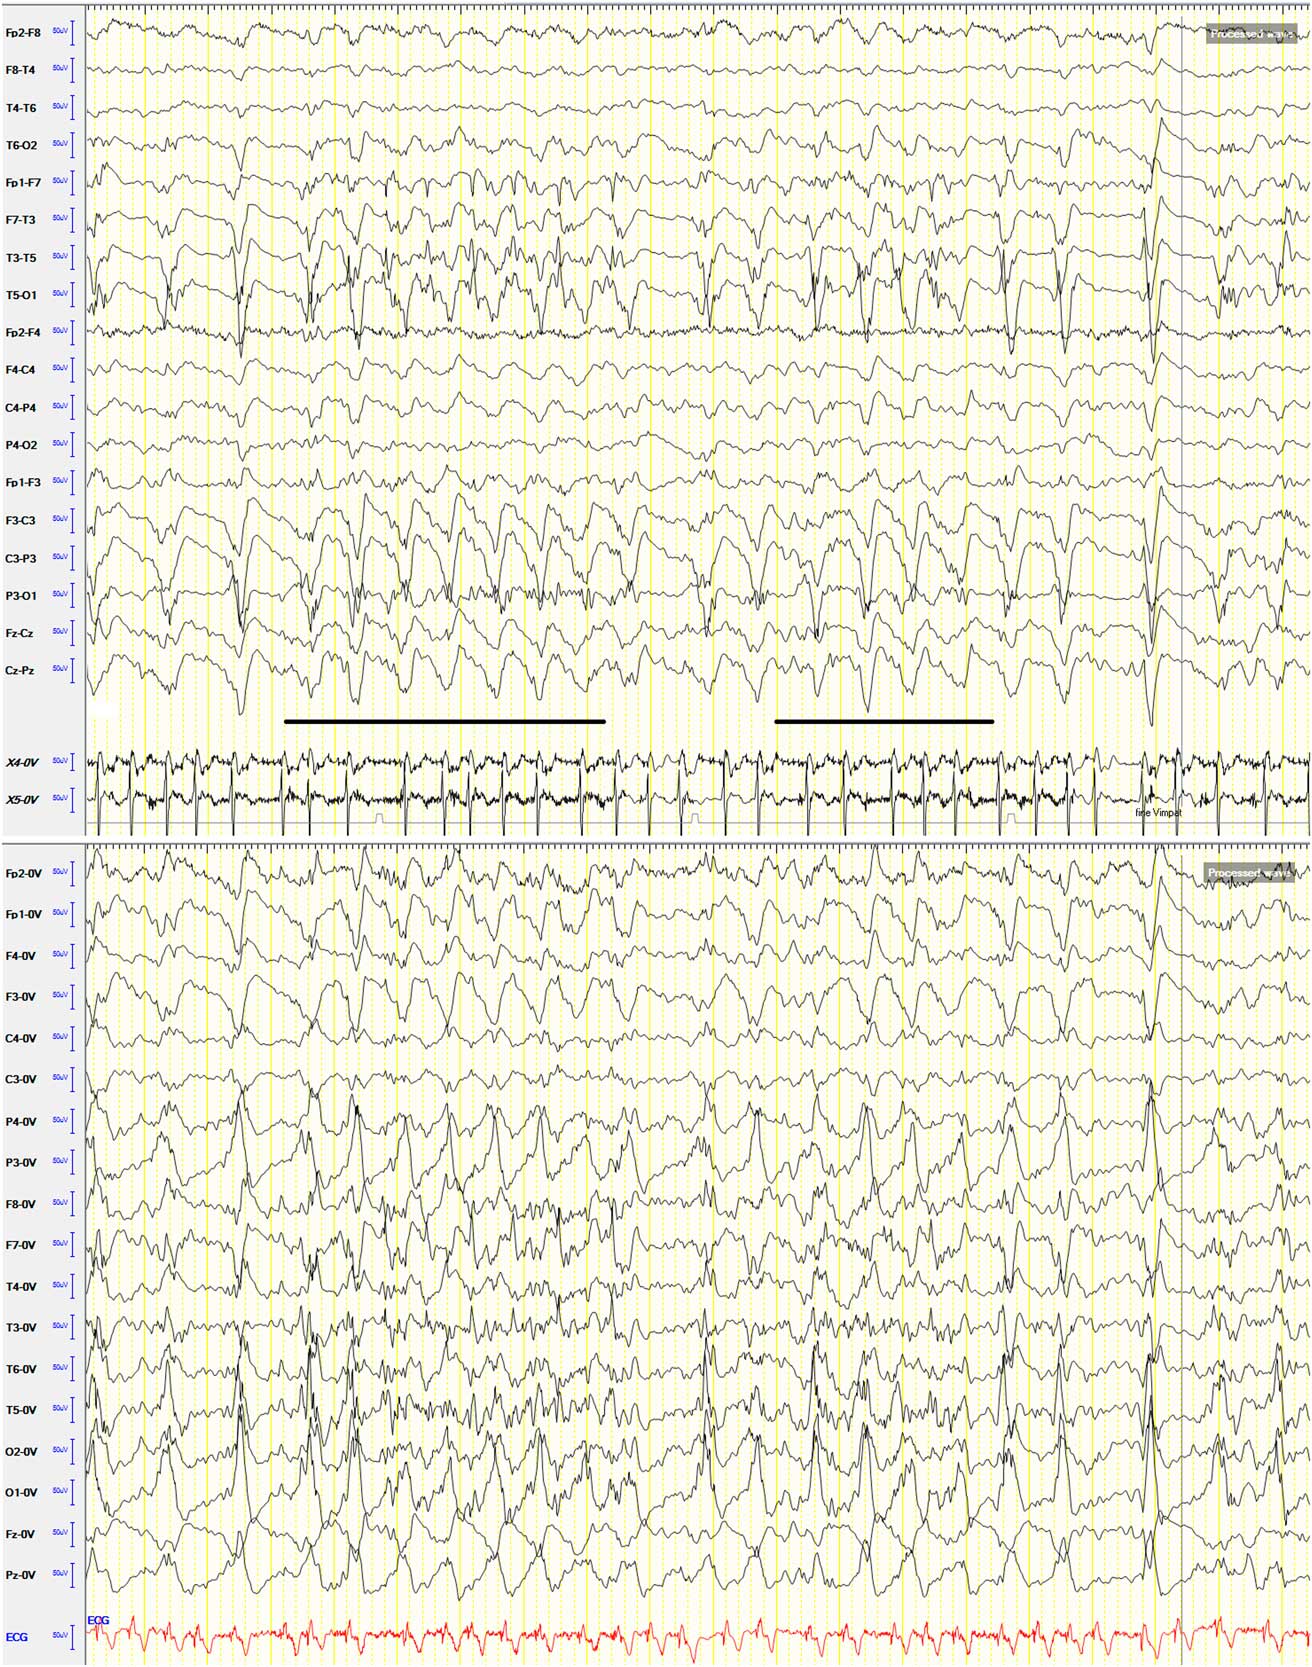

A 91-year-old man was admitted to our hospital with an acute right-sided hemiplegia and somnolence, which had appeared the day before. On admission, myoclonic jerks of the right hemibody were noticed, which promptly stopped after levetiracetam (1000 mg intravenous) administration. His medical history was notable for severe Alzheimer's disease (diagnosed 22 years earlier), chronic vascular encephalopathy with parkinsonism, moderate renal failure, and pancreatic carcinoma. The head CT scan showed ischemic lesions in the left hemisphere, more prominent in the fronto-parietal and temporal lobe, with marked chronic vascular encephalopathy and leukoaraiosis (Figures 1 and 2); the radiological features of the left temporal hypodensity were suggestive of a subacute cerebral infarction. The day after the admission, continuous involuntary contractions of the trunk were noted. Neurological examination showed continuous involuntary and rhythmic jerks involving the abdominal muscles, not spreading to other parts of the body (video). The electroencephalogram (EEG) (Figure 3) revealed rhythmic epileptiform discharges of triphasic/diphasic morphology admixed with polyspikes confined to the left hemisphere (Supplementary material). The most prominent epileptiform abnormalities were localized, over the left posterior temporo-parieto-occipital area. Equipotentiality of epileptiform discharges occurred between electrodes P3 and O1, sometimes with maximal amplitude over O1>P3≥T5>T3, C3 (more evident in referential montage). There were also independent epileptiform discharges located anteriorly, close to the anterior Sylvian region in the left fronto-temporal area, sometimes showing phase reversal at F7 or equipotentiality between F7 and T3. A periodicity (frequency of about 1 Hz) was sometimes evident in epileptiform discharges occurring in both posterior and anterior regions (i.e., lateralized periodic discharges). The EEG recording also showed brief ictal transitions seen maximally over the left posterior hemispheric structures, especially around T5. Overall, the EEG showed anterior and posterior areas of epileptogenicity, more marked in the left posterior temporo-parieto-occipital region. The myoclonic movements were not synchronous with the rhythmic epileptiform discharges. A concomitant electromyographic recording of the muscles of the abdominal wall showed bursts of quasirhythmic asymmetric polymorphic motor potentials of the right abdominal recti muscles, with a duration lower than 100 ms and a frequency of 0.5-1 Hz. The movements attenuated after intravenous administration of lorazepam (4 mg) and levetiracetam (2000 mg), but then reappeared. The patient died of cardiac arrest the following day.

Figure 3 EEG shown in the longitudinal bipolar and referential (common average reference) (below) montage; sensitivity: 7 μV; low-frequency filter: 0.53 Hz; high-frequency filter: 70 Hz. Speed: 20 seconds/page. EMG recording with surface electrodes from both abdominal recti muscles: X4-0V: left rectus abdominis muscle; X5-0V: right rectus abdominis muscle. The most prominent epileptiform abnormalities are localized over the left posterior temporo-parieto-occipital area. Equipotentiality of epileptiform discharges can be seen between electrodes P3 and O1, sometimes with maximal amplitude over O1>P3≥T5>T3, C3 (more evident in referential montage). There are also independent epileptiform discharges located anteriorly, close to the anterior Sylvian region in the left fronto-temporal area, sometimes showing phase reversal at F7 or equipotentiality between F7 and T3. A periodicity (frequency of about 1 Hz) can be observed in epileptiform discharges occurring in both posterior and anterior regions. There are also brief ictal transitions seen maximally over the left posterior hemispheric structures (underlined in the longitudinal bipolar montage), especially around T5.

It is noteworthy that in our patient the most prominent epileptiform abnormalities were recorded over the left posterior temporo-parieto-occipital area, whereas minor abnormalities were seen more anteriorly, in the left fronto-temporal region. The periodicity of epileptiform discharges occurring in both posterior and anterior regions, together with the lack of evolution in discharge amplitude, frequency, morphology, and distribution, is consistent with lateralized periodic discharges in the setting of an acute ischemic stroke. Of note, the myoclonic movements observed in this patient were not synchronous with the rhythmic epileptiform discharges. A strict neurophysiological association between this epileptiform activity and the myoclonic jerks is therefore difficult to prove with certainty. At least 10 cm2 of synchronous cortical activity is required to record an ictal rhythm on scalp EEG,Reference Tao, Ray, Hawes-Ebersole and Ebersole 6 and this explains why in more than 50% of EPC cases the scalp EEG is completely normal.Reference Bien and Elger 2 Furthermore, this dissociation between epileptiform discharges over the motor cortex and the motor correlates can be also owing to vertical inhibition.Reference Elger and Speckmann 7 In this phenomenon, spiking in lamina V following local penicillin administration leads to contralateral twitching without concomitant epileptiform activity recorded on the cortical surface. A motor correlate of epileptic activity was observed only when epileptic discharges involved the superficial and deep cortical layers.Reference Elger and Speckmann 8 The EEG recording also showed brief ictal transitions seen maximally over the left posterior hemispheric structures, especially around T5 (Figure 3), suggesting that these graphoelements might represent the EEG correlate of symptoms. However, unlike the abdominal jerks, these elements lasted only a few seconds, making a definite temporal and topographic relationship between the EEG activities and myoclonus difficult to demonstrate. Overall, it is therefore possible that in our patient the myoclonic jerks of the abdominal musculature actually had no (or very minimal) EEG correlate, and that the lateralized periodic discharges resulted from the acute cerebral infarct (and the concomitant severe underlying leukoaraiosis) but were unrelated to clinical symptoms. If so, the absence of a straight correlation between myoclonic movements and epileptiform discharges prevents a precise anatomical localization of the epileptogenic zone underlying EPC.